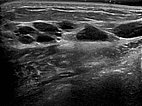

Umschriebene, makrozystische Malformation an der Bauchwand im Ultraschall. Beachte die echofreie Flüssigkeit in den mit Lymphe gefüllten, dünnwandigen zystischen Räumen.

Ultraschall der Bauchwand, etwas weiter kaudal. Hier sind die zystischen Anteile der Lymphatischen Malformation kleiner. Die Läsion liegt jedoch weiterhin extraperitoneal.

In der Ultraschallkontrolle 6 Monate nach der 2. Therapie sind nur noch sehr kleine zystische Anteile der LM nachzuweisen. Die größeren Zysten sind verschlossen. Da die Patientin asymptomatisch ist können diese bei einer an sich benignen Läsion belassen werden.